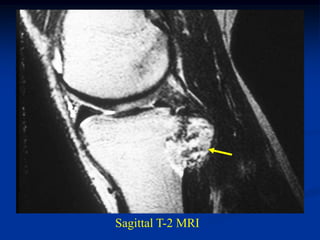

Case #120

38 year female

enchondroma

distal femur

Axial T-2 MRI